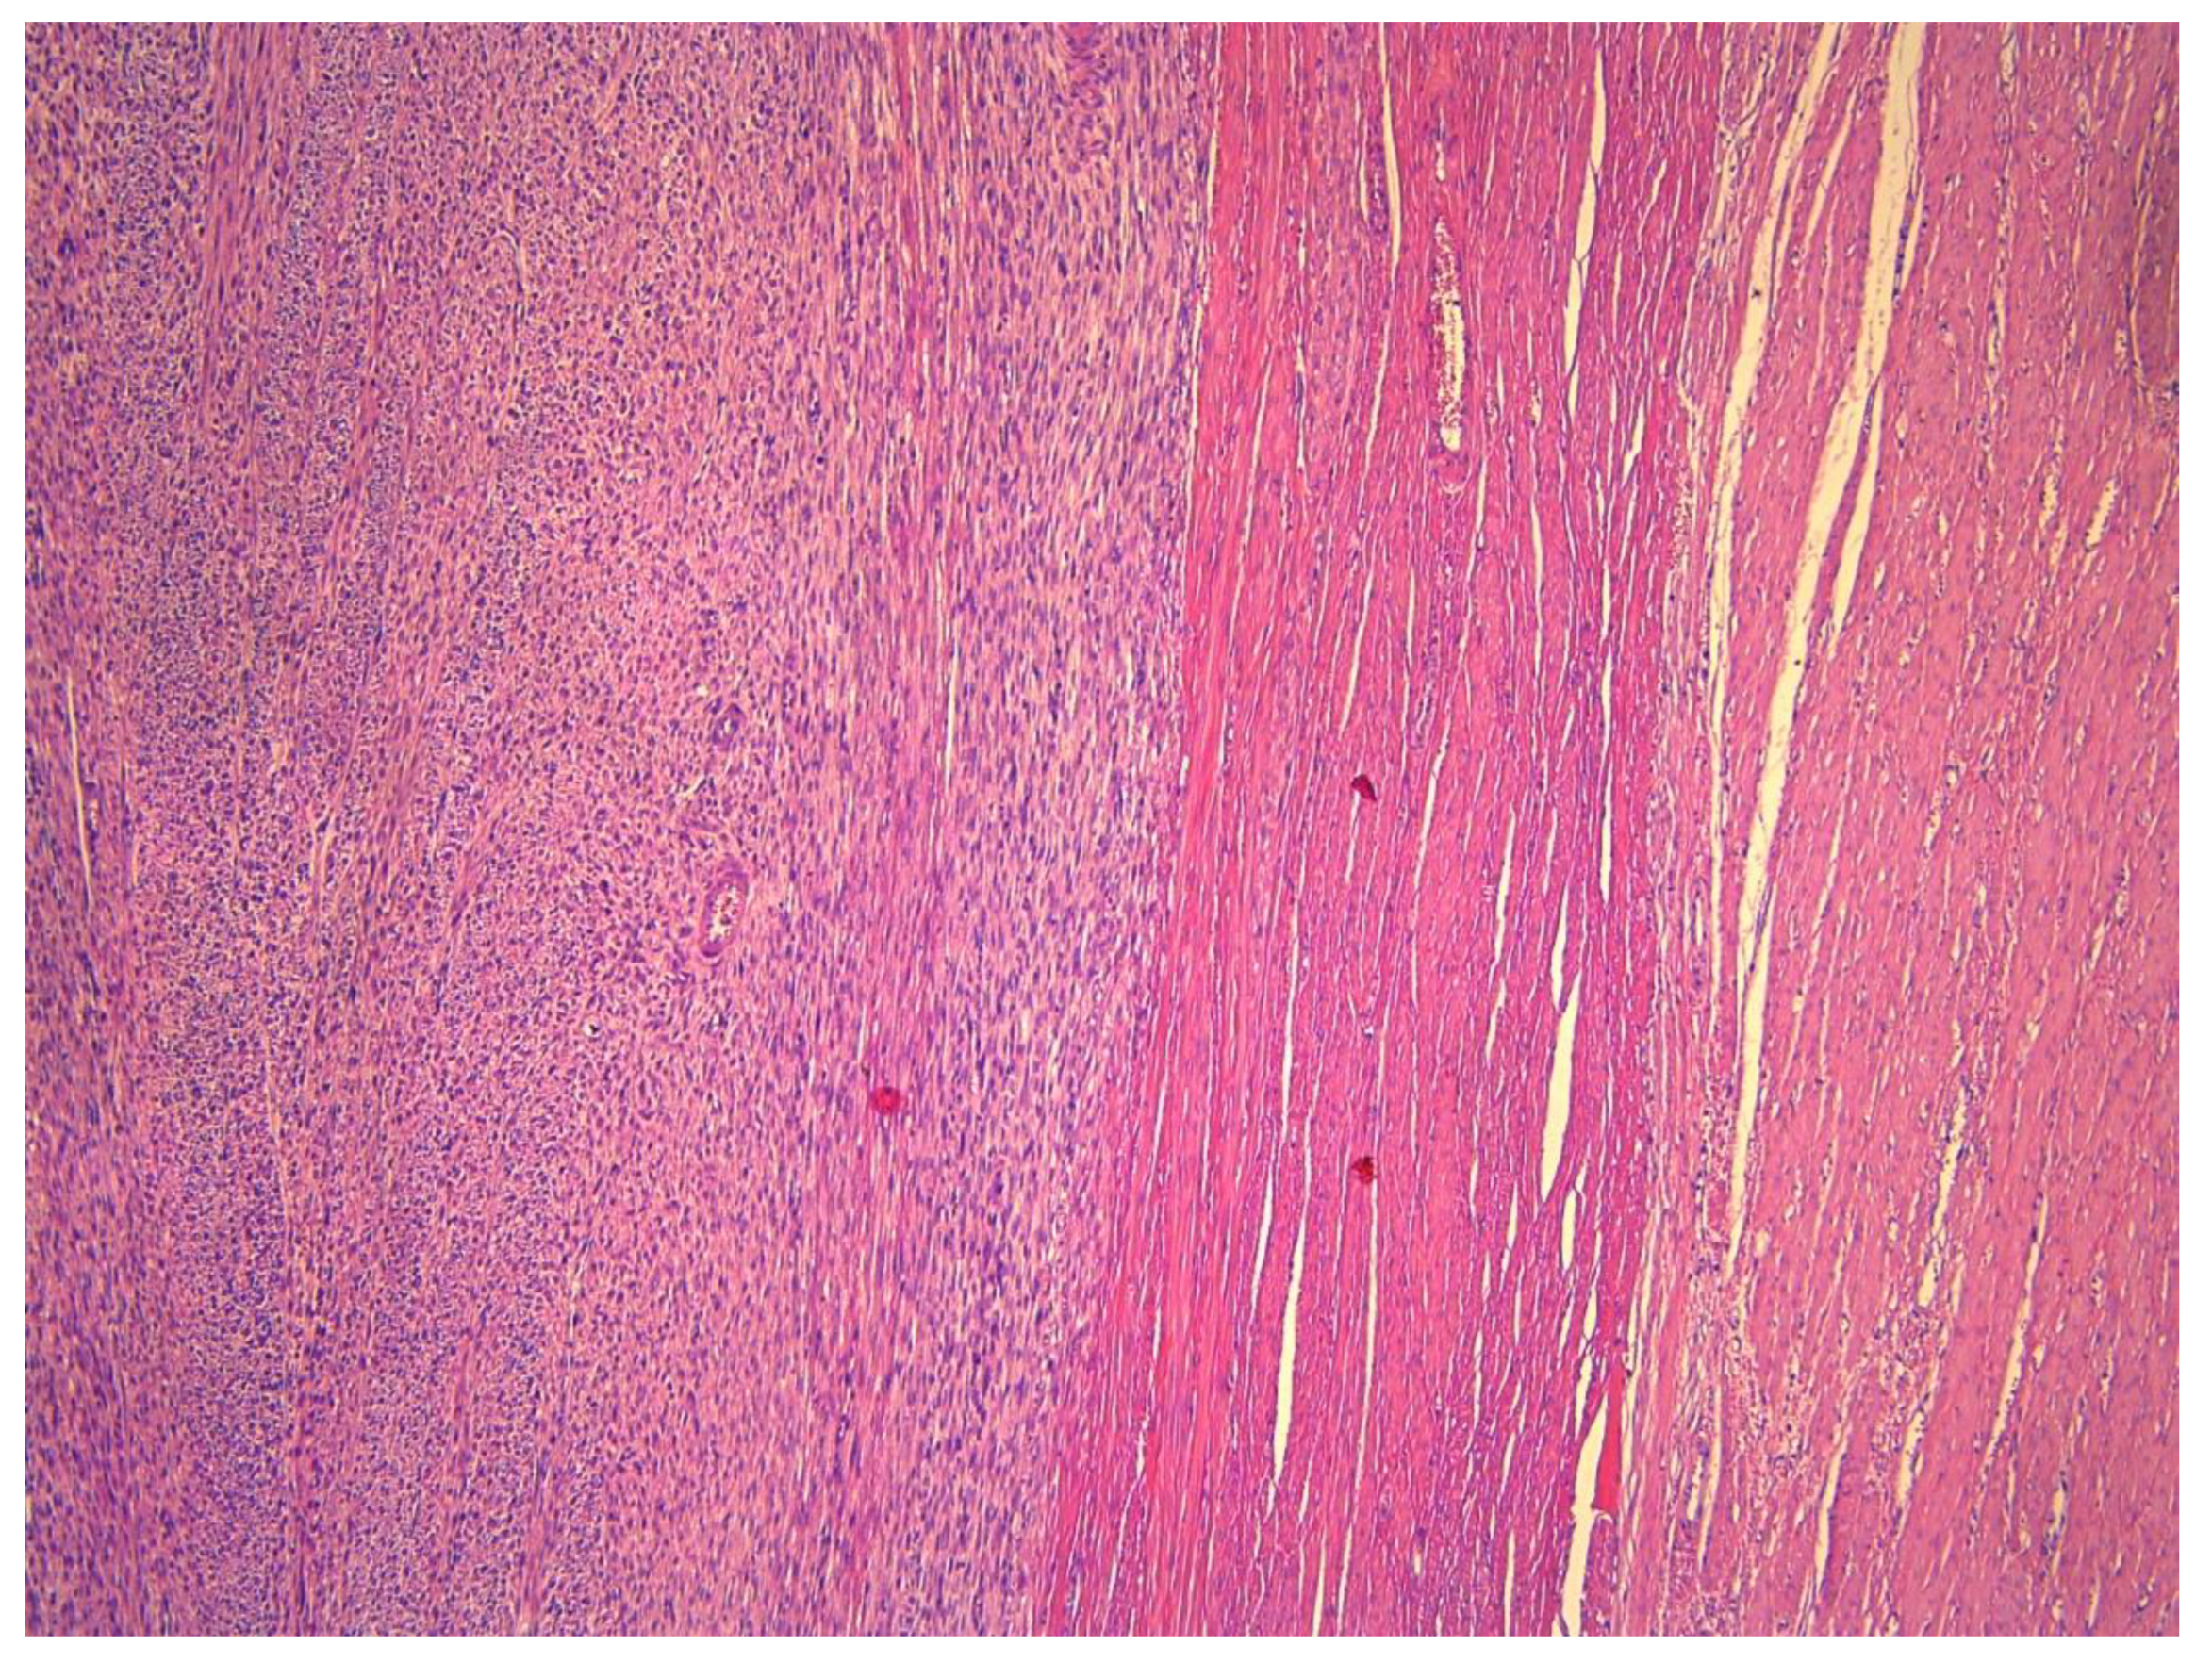

3. Anatomopathological Features

- smooth muscle tumors with focal/multifocal or diffuse cytological atypia (moderate-to-severe), lacking coagulative tumor necrosis and 6–9 mitoses per 10 HPFs (2–4 mitoses/mm2).

- Tumors that lack cytological atypia or raised mitotic count but having unequivocal coagulative tumor necrosis.

- Tumors with elevated mitotic count (>15 mitoses per 10 HPFs or >6 mitoses/mm2) but lacking coagulative tumor necrosis or cytological atypia.

- Tumors with uncertain mitotic count but having diffuse cytological atypia (moderate-to-severe).